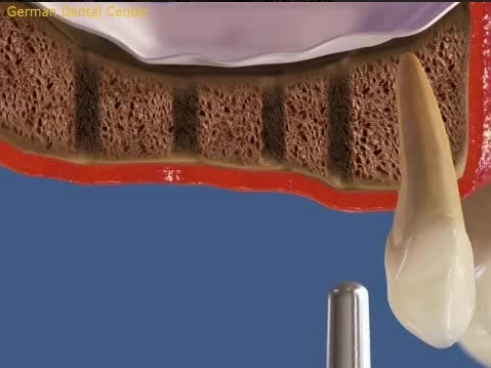

- Имплантация